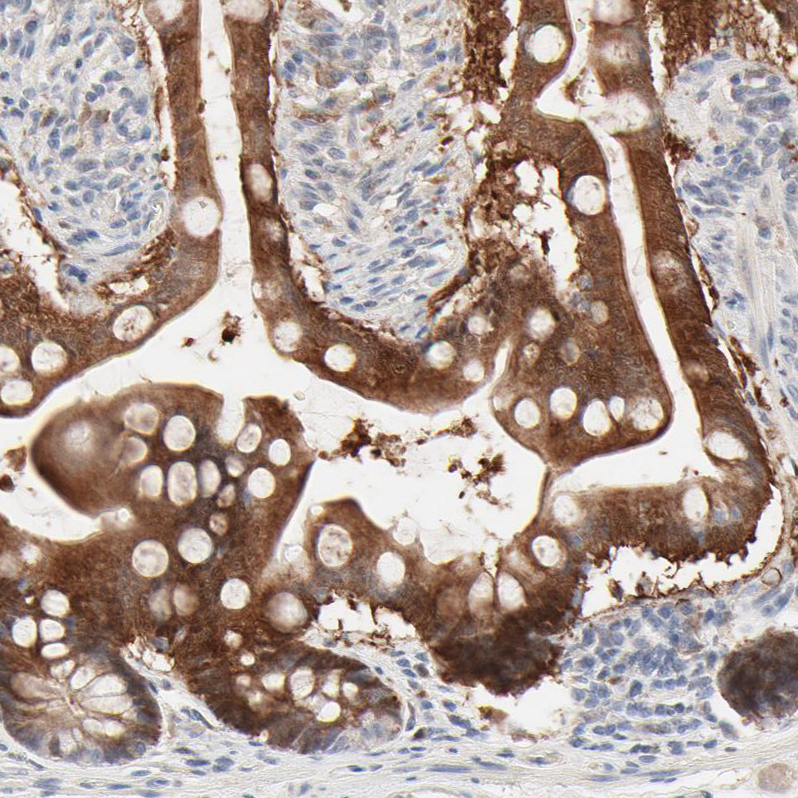

Immunohistochemistry analysis in human pancreas and cerebral cortex tissues using HPA003536 antibody. Corresponding LGALS2 RNA-seq data are presented for the same tissues.